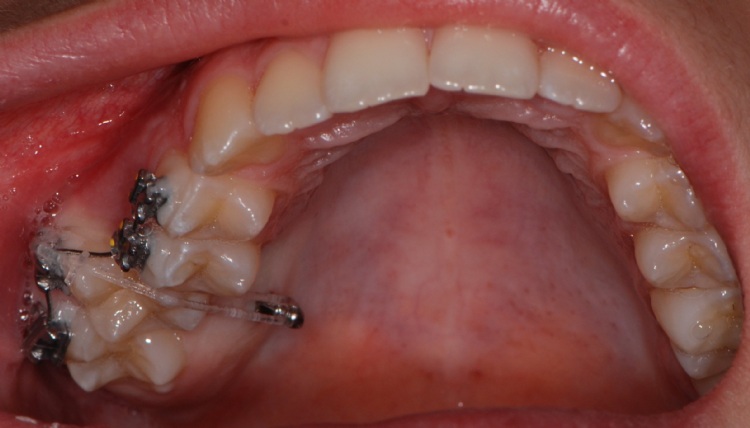

In alcuni casi si può effettuare lo spostamento di elementi dentari tramite l'utilizzo di miniviti ad ancoraggio osseo che consentono di ridurre il numero dei brakets e i tempi della terapia.

La minivite non è fastidiosa e la sua applicazione non provoca dolore.